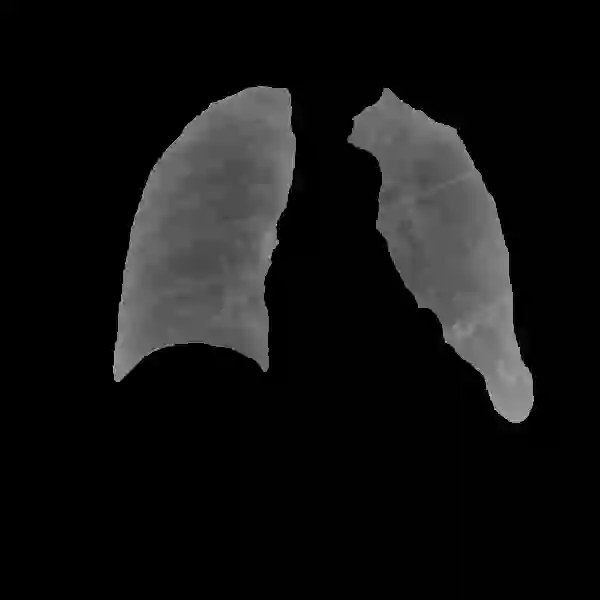

Deep learning technologies have already demonstrated a high potential to build diagnosis support systems from medical imaging data, such as Chest X-Ray images. However, the shortage of labeled data in the medical field represents one key obstacle to narrow down the performance gap with respect to applications in other image domains. In this work, we investigate the benefits of a curricular Self-Supervised Learning (SSL) pretraining scheme with respect to fully-supervised training regimes for pneumonia recognition on Chest X-Ray images of Covid-19 patients. We show that curricular SSL pretraining, which leverages unlabeled data, outperforms models trained from scratch, or pretrained on ImageNet, indicating the potential of performance gains by SSL pretraining on massive unlabeled datasets. Finally, we demonstrate that top-performing SSLpretrained models show a higher degree of attention in the lung regions, embodying models that may be more robust to possible external confounding factors in the training datasets, identified by previous works.